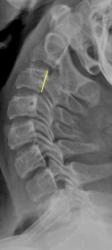

Речь идет не о "подвижности в суставе", а о нестабильности в сегменте. Задний контур С3 помечен "желтым". Обратите внимание, как смещаются позвонки в положении сгибания и разгибания с учетом "заднего контура".